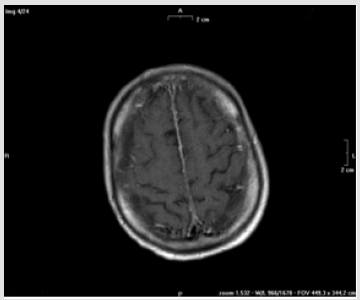

After 48 hours, the patient showed mental state alteration including agitated behavior, confusion and loss of consciousness. He had fever (38.5 °C) but no focal neurological deficits were recorded. Blood pressure was 140/70 mmHg. Laboratory analysis revealed a hemoglobin concentration at 9.7 g/dL, not differently from the previous days, WBC 16150/mm3 with 14000/mm3 neutrophils and platelets 286.000/mm3 C-reactive protein was 100 mg/L and procalcitonin was negative. Renal function tests, serum electrolytes and ammonia blood test were within normal limits. The lumbar epidural catheter was removed, and, in the suspicion of a septic status, a wide spectrum antibiotic therapy was started. Since the neurological status was very compromised a brain CT scan and MRI were performed. The CT scan did not show anomalies, while the MRI detected a diffuse enhancement of the pachymeninx (Figure 1). The EEG revealed a diffuse and aspecific electrical disorder. A diagnostic lumbar puncture displayed a limpid cerebrospinal fluid (CSF), with normal pressure, and the laboratory analysis showed a protein concentration of 2,73 g/L, a glucose concentration of 1.8 mmol/L and leukocytes 10/microL.

Figure 1: Brain MRI section after contrast administration showed a diffuse signal enhancement of the pachymeninx.

To the best of our knowledge, here we have reported for the first time a case of aseptic meningitis related to bupivacaine spinal analgesia administration in a patient with Systemic Sclerosis. According to the data reported above, drug-induced aseptic meningitis is a very rare adverse reaction to several drugs and is diagnosed by exclusion. As already described in literature, clinical manifestations during a drug-induce aseptic meningitis are very aspecific. Fever, headache, confusion, agitation, a stupor or a comatose status may represent the main manifestations, without any common sign of meningeal irritation or photophobia. Neuroimaging is usually noninformative; sometimes Brain MRI may show a diffuse hyper intensity of leptomeningeal spaces [2,5,6]. Cerebro-spinal fluid analysis usually show pleocytosis (hundred to several thousand cells per microliter). Polymorphonuclear predominance is very common, but lymphocytes and eosinophilic presence have also been reported. Moreover, the proteins levels are usually elevated, whereas the concomitant glucose levels remain normal. Of course, bacterial cultures and viral genome research are negative [4-7].

To the best of our knowledge, here we have reported for the first time a case of aseptic meningitis related to bupivacaine spinal analgesia administration in a patient with Systemic Sclerosis. According to the data reported above, drug-induced aseptic meningitis is a very rare adverse reaction to several drugs and is diagnosed by exclusion. As already described in literature, clinical manifestations during a drug-induce aseptic meningitis are very aspecific. Fever, headache, confusion, agitation, a stupor or a comatose status may represent the main manifestations, without any common sign of meningeal irritation or photophobia. Neuroimaging is usually noninformative; sometimes Brain MRI may show a diffuse hyper intensity of leptomeningeal spaces [2,5,6]. Cerebro-spinal fluid analysis usually show pleocytosis (hundred to several thousand cells per microliter). Polymorphonuclear predominance is very common, but lymphocytes and eosinophilic presence have also been reported. Moreover, the proteins levels are usually elevated, whereas the concomitant glucose levels remain normal. Of course, bacterial cultures and viral genome research are negative [4-7].